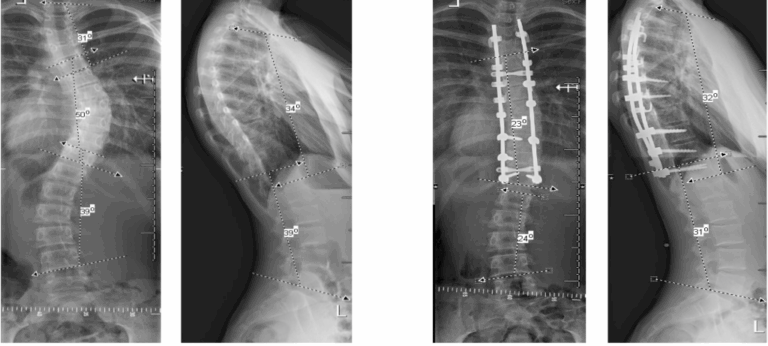

Operatie

In bepaalde gevallen is een operatie de beste optie. Moderne scoliose chirurgie heeft goede resultaten: de rug wordt rechter, ziekenhuisopname is meestal kort, en je kunt binnen enkele maanden weer bijna alle activiteiten oppakken.